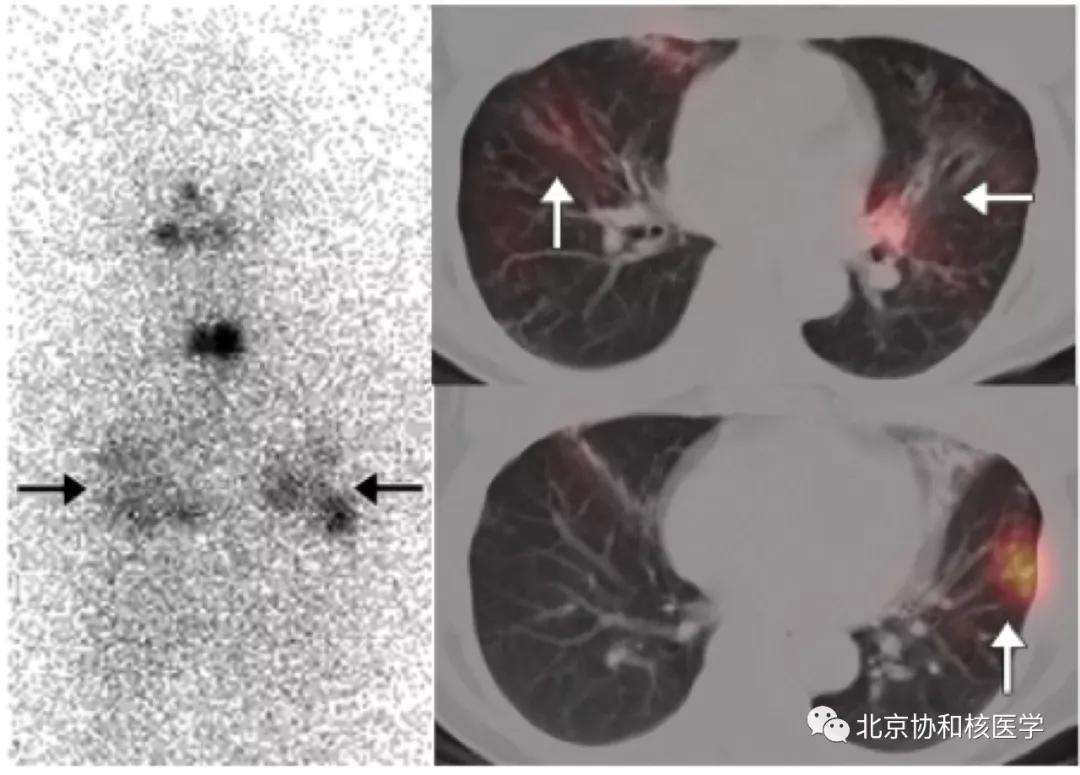

63岁女性,甲状腺癌病史,肺内不典型分支杆菌感染所致碘摄取:

肺鳞癌所致碘摄取(后位图像),同时可见颈部甲状腺残余病灶: